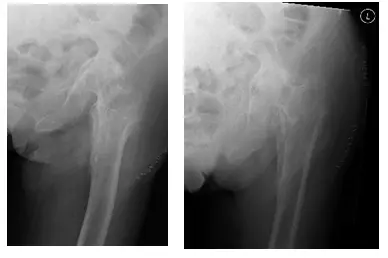

La paciente es una mujer de 75 años que acudió a nosotros con dolor intenso en la cadera izquierda tras someterse a una fijación interna de reducción abierta (ORIF) de la cadera izquierda. El paciente vino con radiografías para revisar, como se muestra a continuación,...